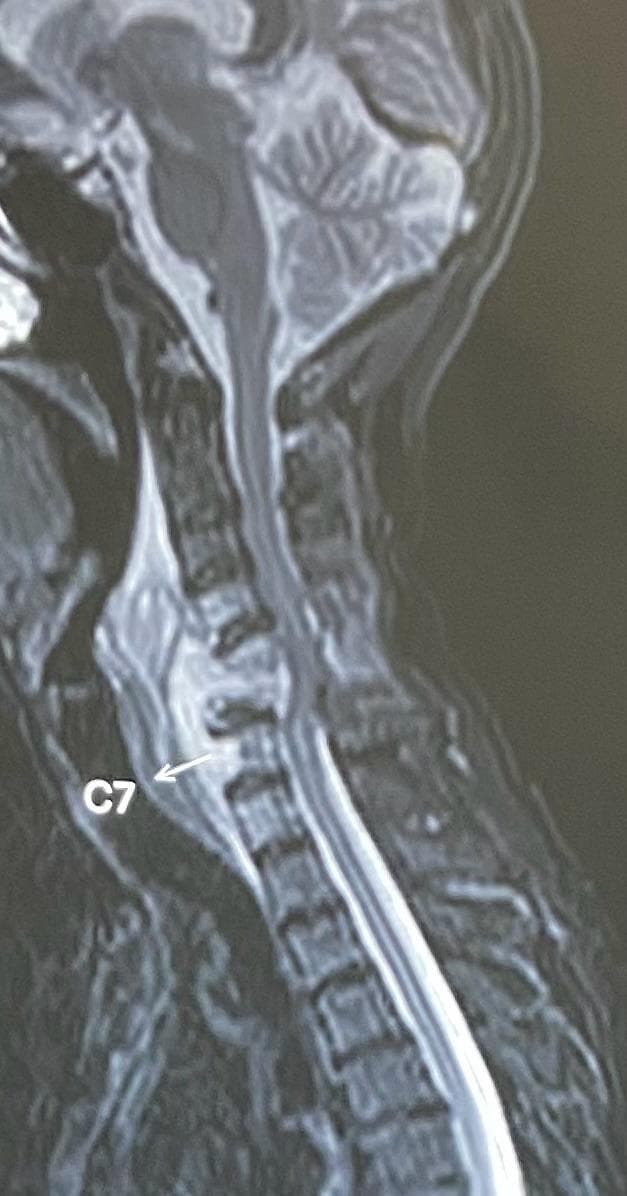

A 65-year-old lady came to us with severe weakness in all four limbs. She was unable to move her hands or legs and had gradually lost her independence. Investigations, including MRI, revealed collapse of the C5 and C6 vertebral bodies due to spinal tuberculosis. A large epidural abscess was pressing on her spinal cord, leading to quadriplegia (paralysis of all four limbs). It was a critical situation, as without urgent treatment, the chances of recovery were very slim. After careful evaluation, we planned an anterior cervical corpectomy of C5 and C6, removal of the diseased bone and abscess, and reconstruction with a bone graft from her iliac crest along with a plate for stability.